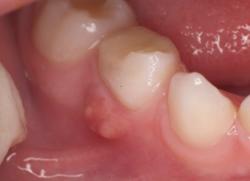

Во-вторых, если ребенок раскроет рот, то вы обнаружите над зубом на десне шишку – сам очаг воспаления. Это образование заполнено гноем. Сама шишечка очень болезненна, маленькие пациенты страдают от сильнейшей зубной боли. В некоторых случаях поднимается температура, как ответ организма на инфекцию.